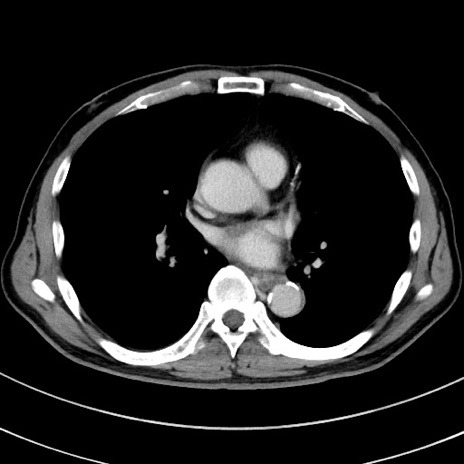

冠状断像

【症例】 60歳代男性

【主訴】 黒色吐物

【現病歴】 4日前から嘔気自覚、2日前の朝食後にも嘔気あり、自分で手で嘔吐反射起こし嘔吐したところ血が混ざっていたため受診。

【既往歴】 5年前汎発性腹膜炎を伴う急性虫垂炎で手術、高血圧、前立腺肥大症、高脂血症

【身体所見】 腹部正中に手術癩痕あり 腹部平坦・軟圧痛なし膨満感あり

【データ】WBC 8400、CRP 4.54